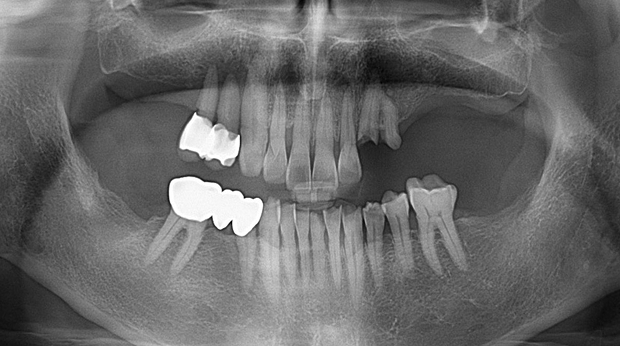

매복 사랑니 발치

임플란트와 사랑니 발치는 외과적 시술로 잇몸을 절개하는 외과적 시술은

짧으면 짧을 수록 시술 후 붓기와 통증이 최소화됩니다.

치과의사 경력 14년차 구강외과 전문의가 빠르고 안전하게, 아프지 않게 수술해 드립니다.